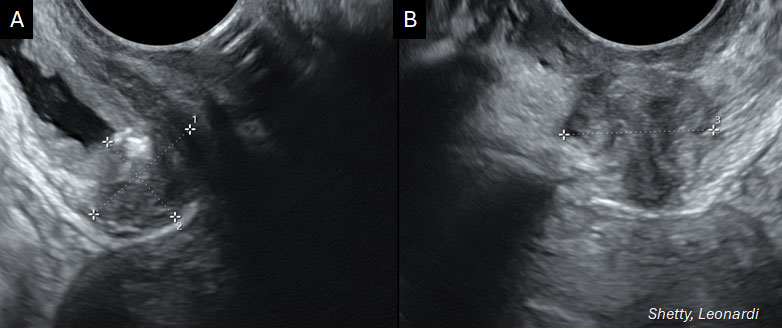

The other main areas of the posterior compartment are the USLs, the most common site of DE and SE, and the posterior vaginal fornix (PVF).51 The USL is around 12–14 cm long and extends caudally from the posterior cervix and vaginal dome to the sacrum.52 USL DE can be difficult to visualize laparoscopically as POD obliteration may obstruct the view highlighting the role of preoperative imaging (Figure 6).53 If lesions are found, the extent of parametrial and/or torus uterinus (posterior insertion of USLs into the posterior cervix) involvement should be assessed as well (a detailed guide for ultrasound diagnosis of USL endometriosis diagnosis has been published previously54). Compared to bowel endometriosis, TVS assessment of USLs has lower sensitivity, and contrast media to enhance visualization should be explored.33,34 The poorer diagnostic test performance for USL DE warrants adoption of new approaches to visualize these important structures. PVF endometriosis is suspected if the PVF is thickened or if a discrete nodule is found in the hypoechoic layer of the vaginal wall. Diagnostic potential of imaging for PVF is important but findings on physical examination must also be considered. The rectovaginal septum, while often thought of as a common place for DE, is indeed an unusual location. In addition to anatomical distortion that propagates confusion, nomenclature differences around the world may lead to some confusion. In some regions, posterior compartment DE is referred to as “rectovaginal” DE. The similarity of rectovaginal DE and rectovaginal septal DE leads to this misunderstanding. While the use of the term rectovaginal DE made sense before imaging could better localize nodules in the distorted posterior compartment, it is a term that should now be retired. Rectovaginal DE does not actually need to directly involve the rectum or vagina for the term to be used. In such cases, the term can be misleading regarding the exact type of surgery required to treat the disease.

.jpg?1645173)

6

Transvaginal ultrasound images (sagittal (A) and transverse (B) views) showing a hypoechoic lesion (calipers) along the uterosacral ligament, characteristic of deep endometriosis with loss of normal echotexture and contour distortion.